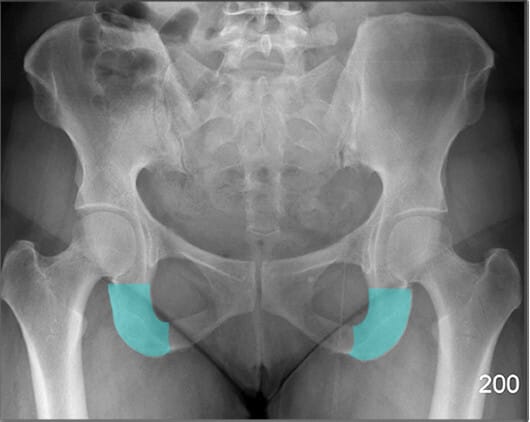

폐쇄공 (Obturator Foramen)

| 폐쇄공 (Obturator Foramen) |

| ✅ 치골과 좌골 사이에 위치한 크고 타원형의 개구부로, AP view에서는 골반 하단 양측에 대칭적인 투과성 음영으로 보입니다. |

| 🔴 골반 골절에서 비대칭이나 모양 변화가 나타날 수 있는 부위입니다. |